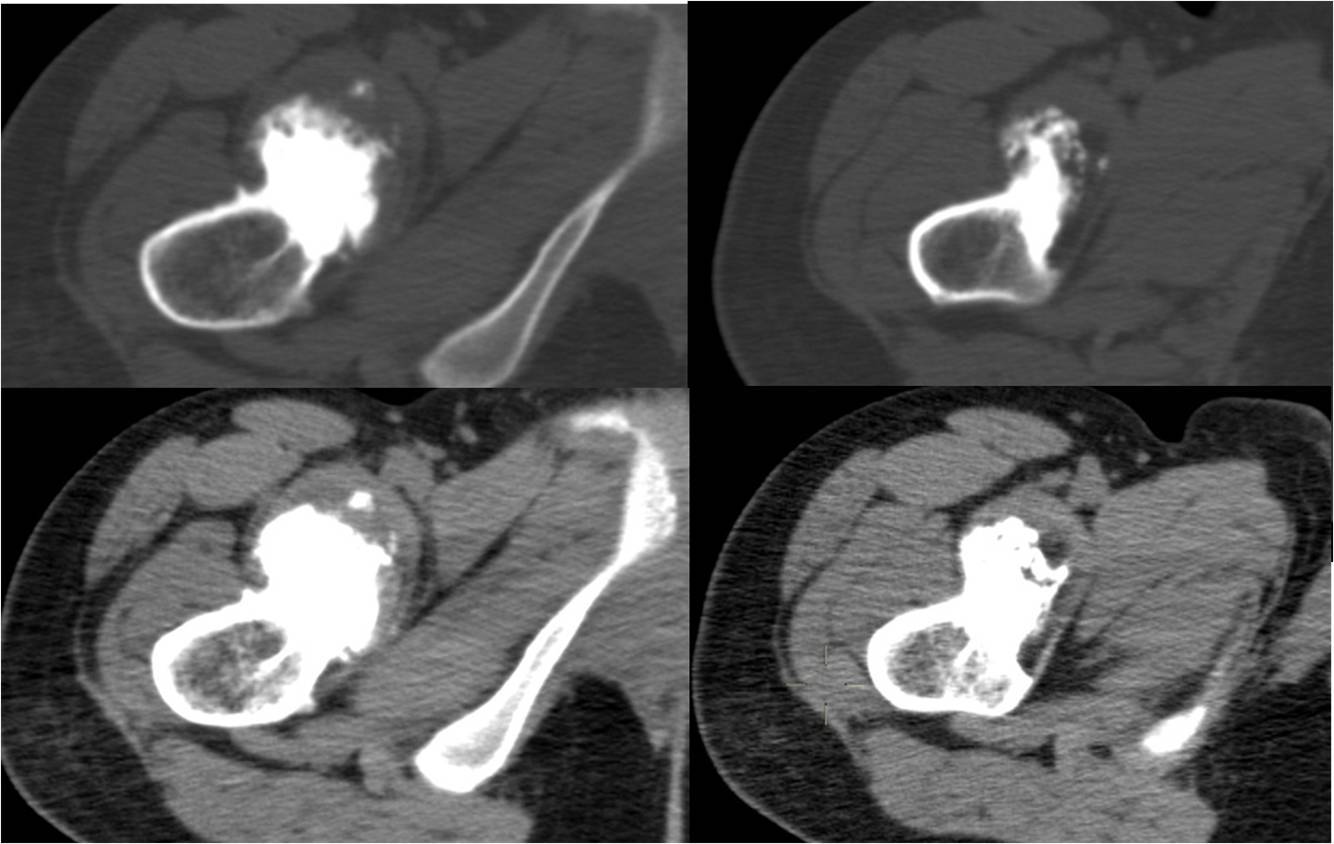

2、CT、MRI扫描检查

显示有脊柱裂,脊髓和神经畸形,局部粘连。